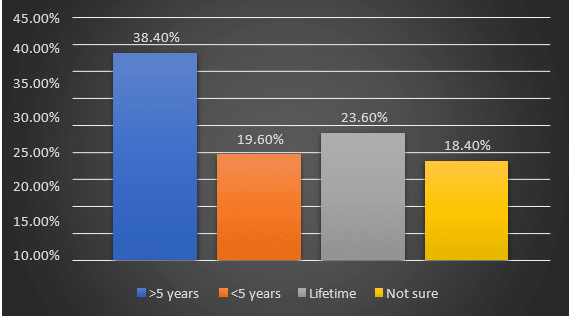

Nurses’ Experiences with Ethical Dilemmas in Critical Care Settings: A Mixed-Method Study at Saidu Teaching Hospital

Background: Critical care nurses (CCNs) routinely experience multiple ethical dilemmas that force them to test their ability to make decisions...Read More